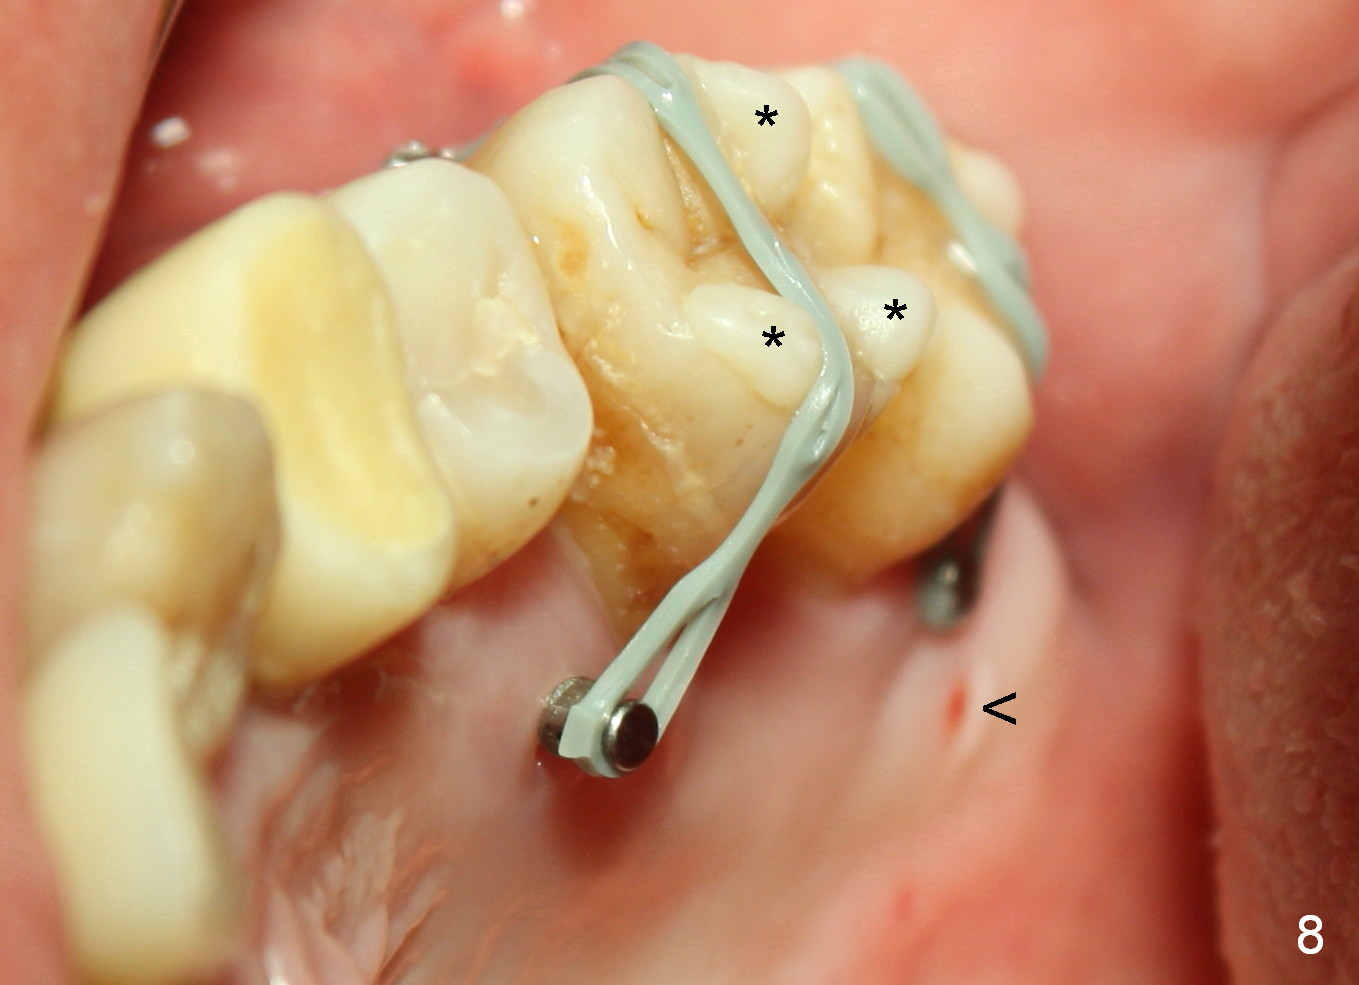

A 41-year-old man has chronic periodontits with bruxism. The teeth #14 and 15 are supraerupted (Fig.1 arrows) with furcal lesion (Fig.2 (CT) *). These 2 molars have guarded to poor prognosis. Due to insurance benefit limitation, we plan to save them temporarily with periodontal surgery so that bone loss would not get worse when the teeth are being intruded. After opposing implant placement (Fig.3), flaps are raised to remove calculus and granulation tissue (Fig.4, no bone graft). Twenty days later, three mini-implants are placed (Fig.5,6). The implant distopalatal to #15 is loose nearly 2 months postop (Fig.7 *) and retightened. The following month the same implant is placed higher for stability (Fig.8). The Intrusion takes <5.5 months (Fig.9,10).